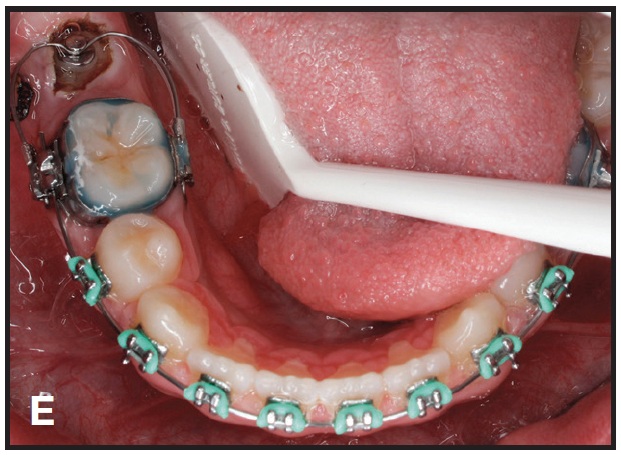

This technique is demonstrated in a 13-year-old female patient with an impacted lower right second molar (D). A U-loop spring was activated after surgical exposure of the tooth (E). Two months later, the second molar had been partially uprighted (F). After three more months of uprighting, the spring was removed and a continuous archwire was placed (G). It took another three months to completely upright the molar using straightwire mechanics, with no side effects on the anchor units (H).